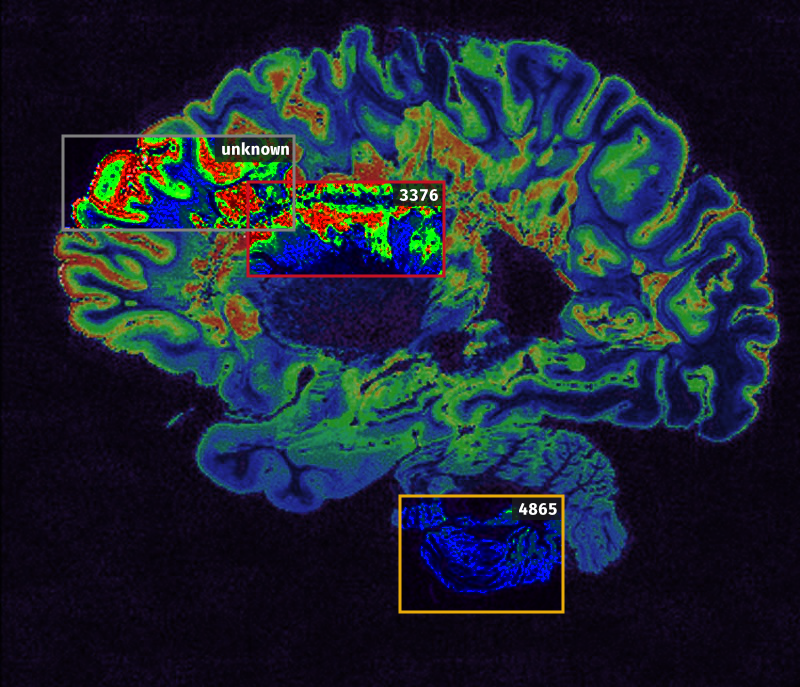

受SCP-CN-2202影响人员的脑部扫描图,异常神经活动区4已标记出。

脑部扫描图为DouglasLiu所作